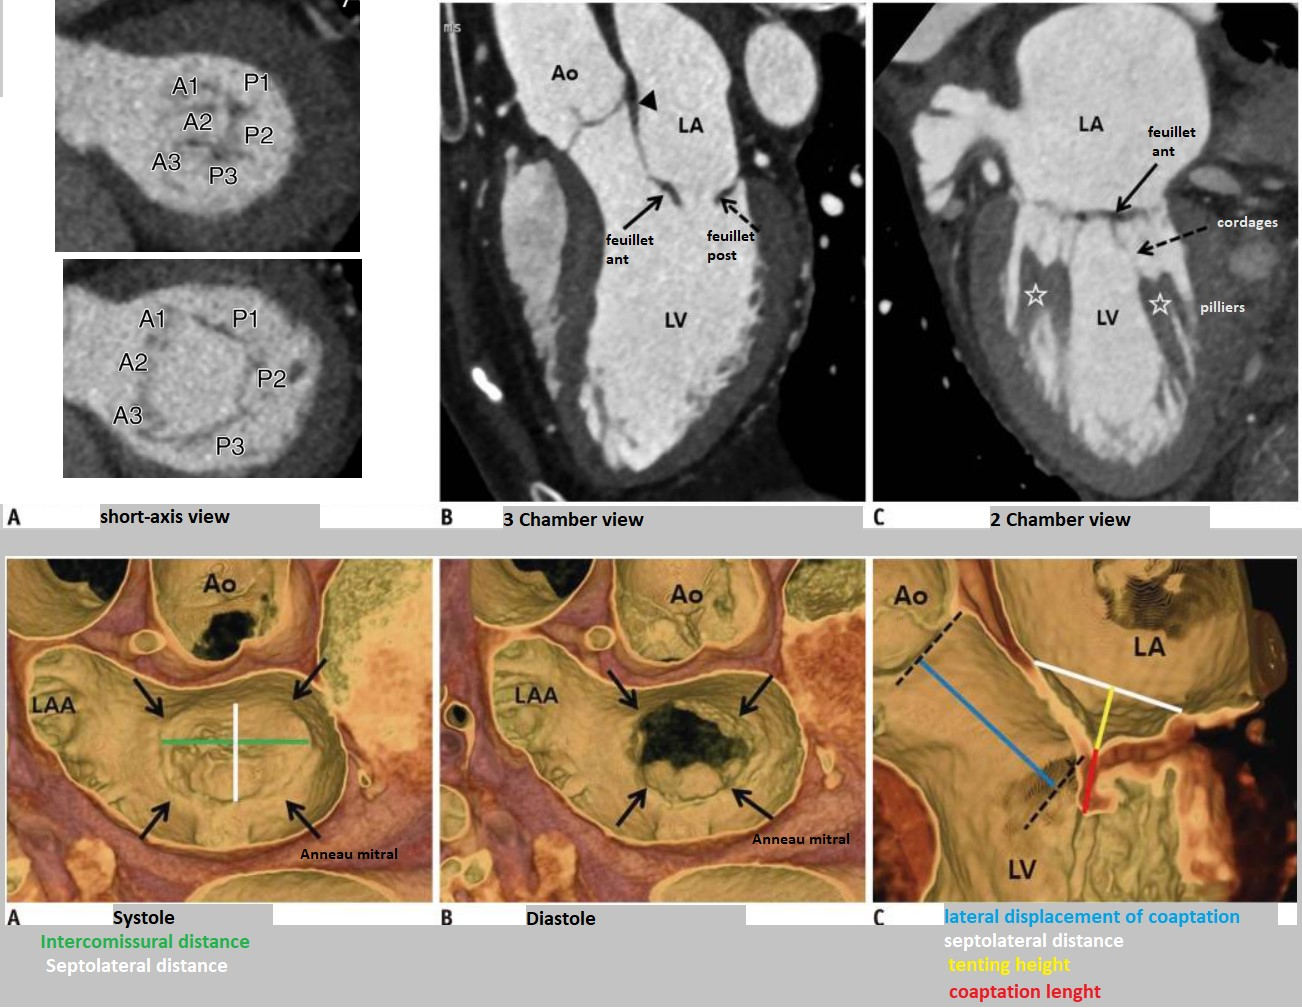

Anatomie

CT

- Prolapsus mitral = Débordement (bowing) en systole de >2mm des feuillets dans l’OG

- Le prolapus est du a la rupture ou l’élongation des cordages

- Epaississement des feuillets (>5mm) fréquemment associée

anatomie anatomy mitral mitrale valve valvulaire anneau mesures bilan feuillet feuillets pilier pillier piliers